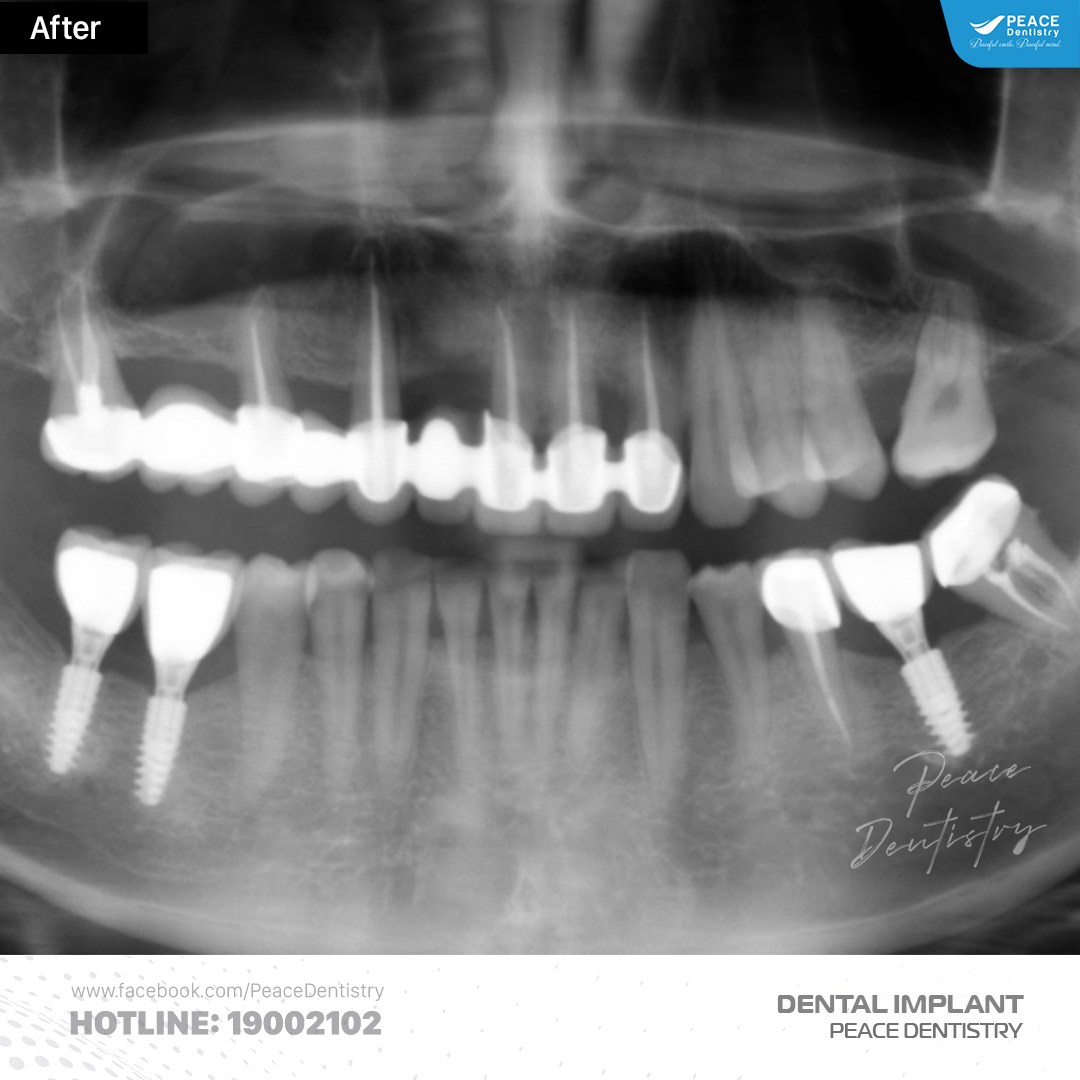

(Hình ảnh Panorex của khách hàng tái khám sau khi trồng implant 5 năm)(**)

(Hình ảnh Panorex của khách hàng tái khám sau khi trồng implant 6 năm)(**)